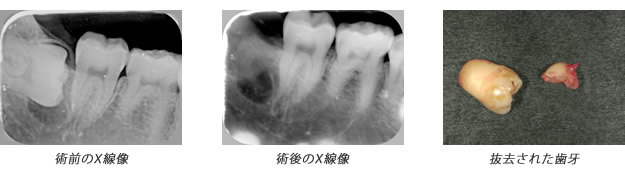

| 上図の抜歯をした際のX線画像 |

歯内療法か?外科的療法か?病理組織的には病変に上皮があれば歯根嚢胞(外科的療法必要)、上皮がなく繊維と血管だけの場合は歯根肉芽腫(歯内療法で治癒可能)と呼ばれますが、実際の所レントゲン(CTを含む)で判断するのは困難です。臨床の現場ではまず歯内療法のみを選択しますが、治癒しない場合は外科的療法(嚢胞摘出&歯根端切除術)に移行するといった流れになることが多いです。 |